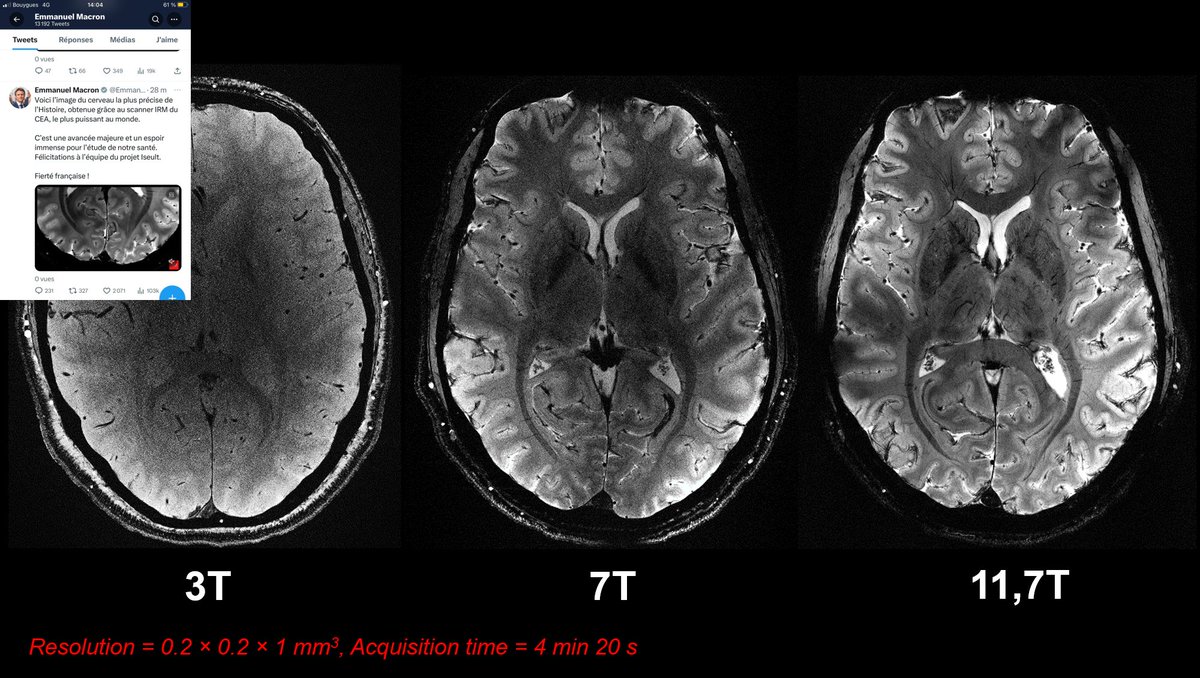

Cognitive Neuroscientist interested in high-level vision, numerical cognition and UHF brain imaging @NeuroSpin_91